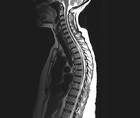

Case Report: Longitudinally Extensive Transverse Myelitis

Ylec Mariana Cardenas, MD; Lakshmi Leishangthem, MDYlec Mariana Cardenas, MD; Lakshmi Leishangthem, MD - Imaging & Testing